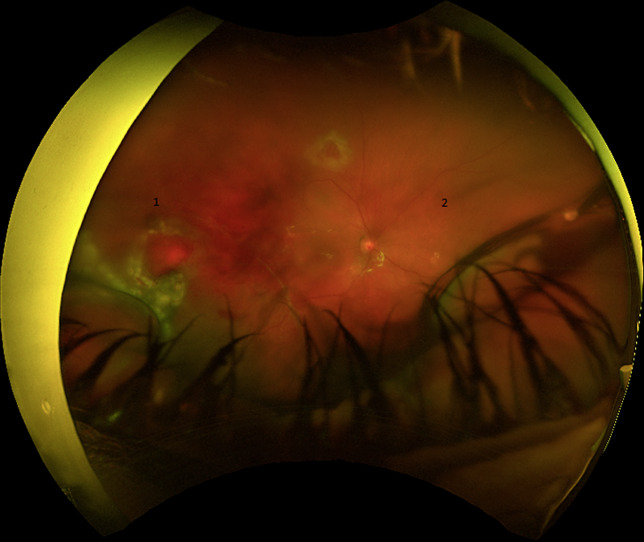

Case presentation: A 48-year-old myopic male presented with a 1-day history of hand motion vision. He was found to have an extensive vitreous hemorrhage with no view of the fundus. On follow-up 4 days later, he continued to have a significant vitreous hemorrhage and a B scan that showed a possible retinal tear. Upon having surgery 7 days later, he was found to have a temporal retinal detachment with subretinal fluid and hemorrhage extending to, but not involving, the macula. His postoperative course was complicated by persistent preretinal and subretinal hemorrhages along with recurrent retinal detachments requiring 2 additional surgeries. He was evaluated by his primary care physician and had a normal thrombotic work-up and all his dietary supplements, including turmeric, were discontinued. At post-op month 2, he continued to improve with resolving subretinal hemorrhage and an attached retina.

Conclusion: This case report describes the extensive and recurrent subretinal hemorrhage that can develop in those patients taking medications or supplements with anticoagulant and/or antiplatelet properties. These antithrombotic agents are not only limited to prescription medications but can also include dietary supplements such as turmeric. It highlights the importance of knowing both the medications and dietary supplements a patient uses as this can affect the long-term outcome.